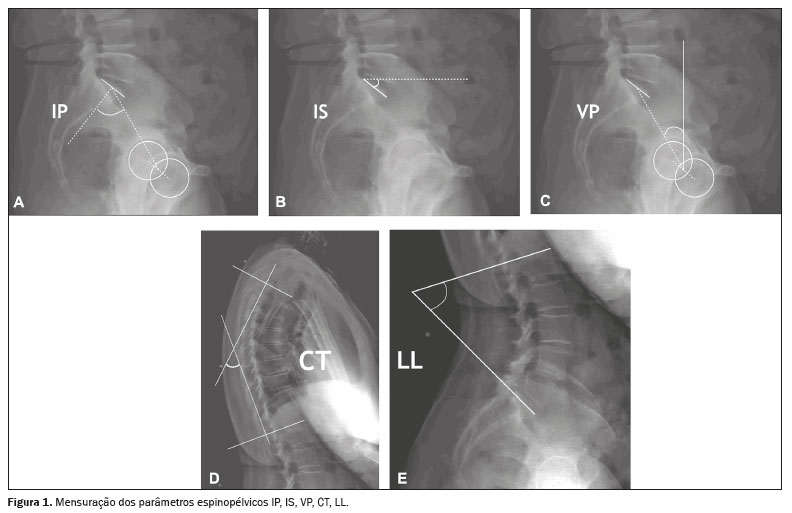

Para mensurar os parâmetros espinopélvicos e ângulos das curvaturas vertebrais foi utilizado o software Surgimap (Nemaris Inc., New York, NY, EUA). Os seguintes parâmetros foram avaliados: inclinação sacral (IS); versão pélvica (VP); incidência pélvica (IP); lordose lombar (LL); cifose torácica (CT); eixo vertical sagital (EVS); ângulo espinossacral (ASS); ângulo T1 pélvico (ATP) e versão global (VG), conforme mostrado nas Figuras 1 e 2. A IS corresponde ao ângulo formado entre a placa da extremidade superior de S1 e a linha horizontal. A VP corresponde ao ângulo formado entre uma linha vertical que se origina no centro da cabeça femoral e uma linha que parte do centro da cabeça femoral para o ponto médio da placa terminal de S1. A IP corresponde ao ângulo formado pela perpendicular ao platô sacral e a linha que conecta o ponto médio deste com o centro de rotação femoral. A LL é a medida do ângulo de Cobb do platô superior de S1 até o platô superior de L1. A CT é a medida do ângulo de Cobb do platô inferior de T12 até o platô superior de T1. O EVS é a medida da distância horizontal entre a linha de prumo de C7 e a linha vertical que passa pelo ponto posterossuperior de S1. O ASS corresponde ao ângulo formado entre a linha que passa do centro de C7 ao centro da placa terminal de S1 e a superfície da placa terminal sacral. O ATP é o ângulo obtido por uma linha formada do centro geométrico das cabeças femorais ao centro do corpo vertebral T1 e uma linha do centro geométrico das cabeças femorais ao centro da placa terminal superior de S1. A VG é definida como o ângulo formado por uma linha do centro da placa final superior sacral ao centro do corpo vertebral C7 e uma linha do centro geométrico das cabeças femorais ao centro da placa terminal sacral(15). Os contornos das cabeças femorais foram marcados e foram traçadas linhas adjacentes ao platô superior de S1, platô superior de L1, platô inferior de T12, platô superior de T1 e platô inferior de C2. A partir dessas marcações, o software calculou automaticamente os parâmetros espinopélvicos e as curvaturas vertebrais.